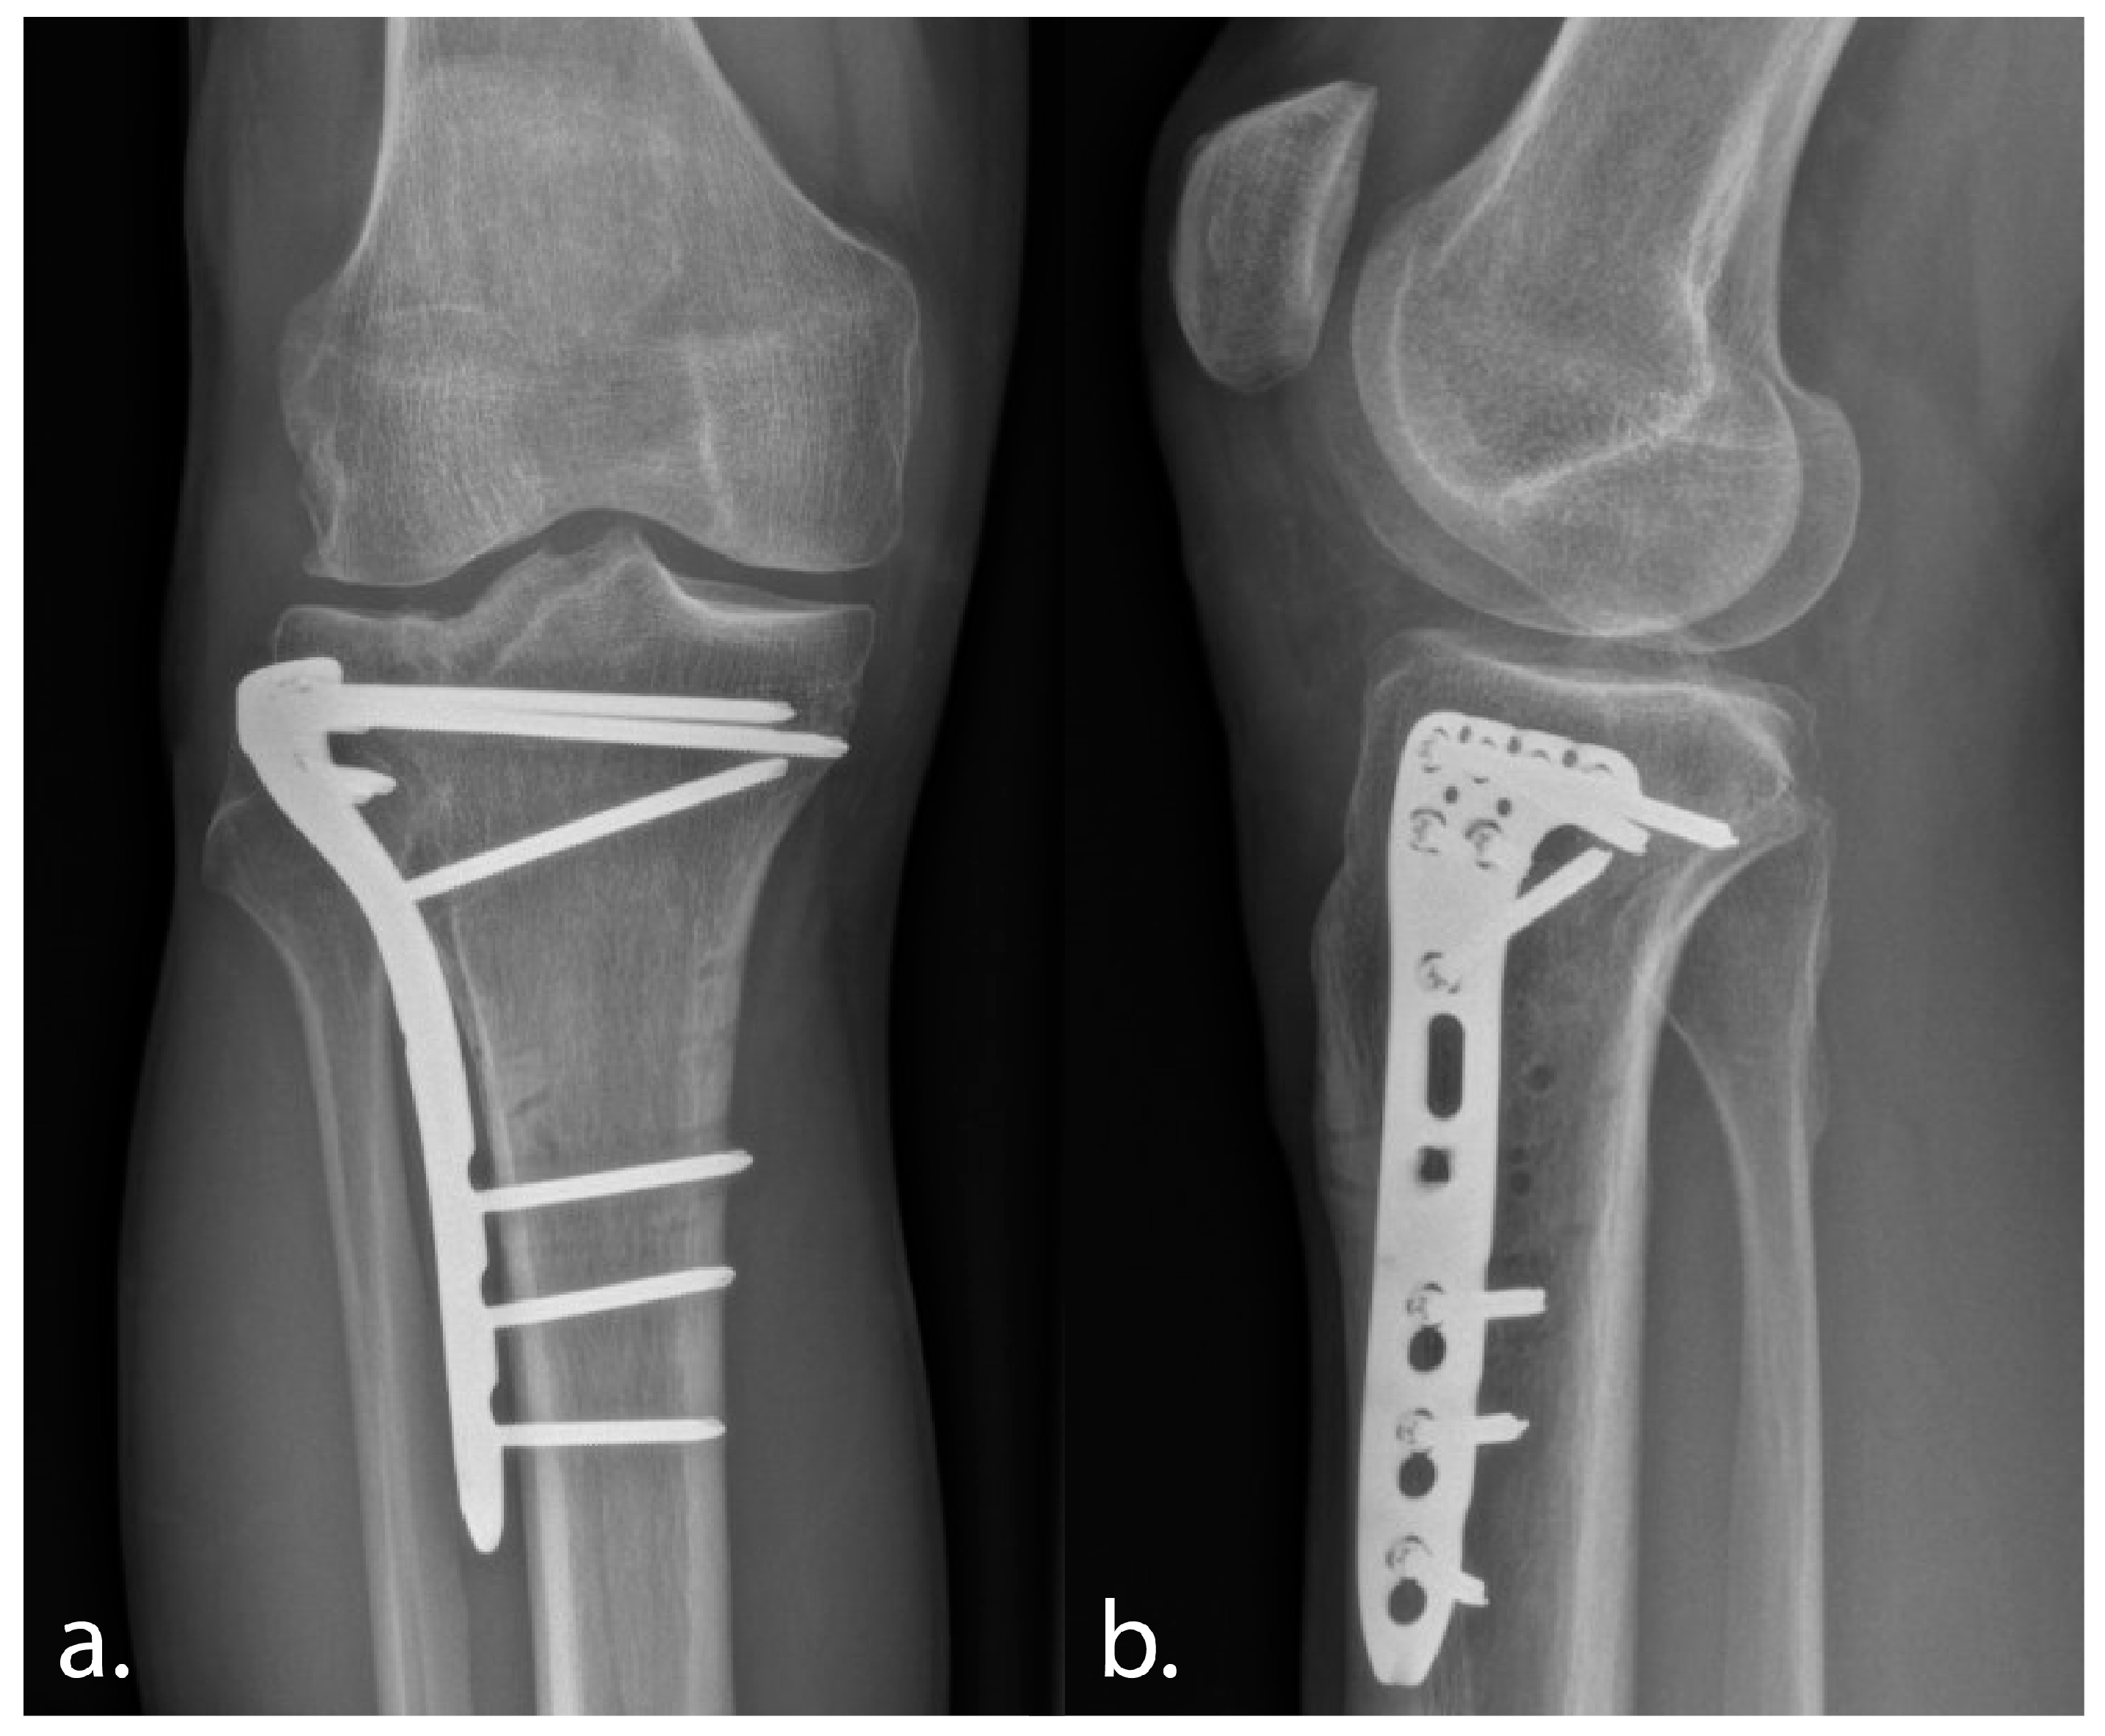

The procedure went without any technical drawbacks or intra-operative surgical complications. Clinically, the patient was satisfied and without pain at 3 months follow-up, regaining full knee flexion. Defect laxity, presented as a subjective feeling of instability resolved for squatting, climbing stairs, or hiking, such as experienced preoperatively. Postoperative radiograph showed quantified improvement of the height of the corrected lateral plateau, resulting in improved tibial alignment (Figure 6).

Figure 6. Postoperative anteroposterior (a) and lateral radiographs (b) at 3 months follow-up demonstrating improved alignment and progressive consolidation.